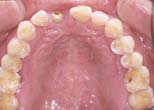

Forced eruption